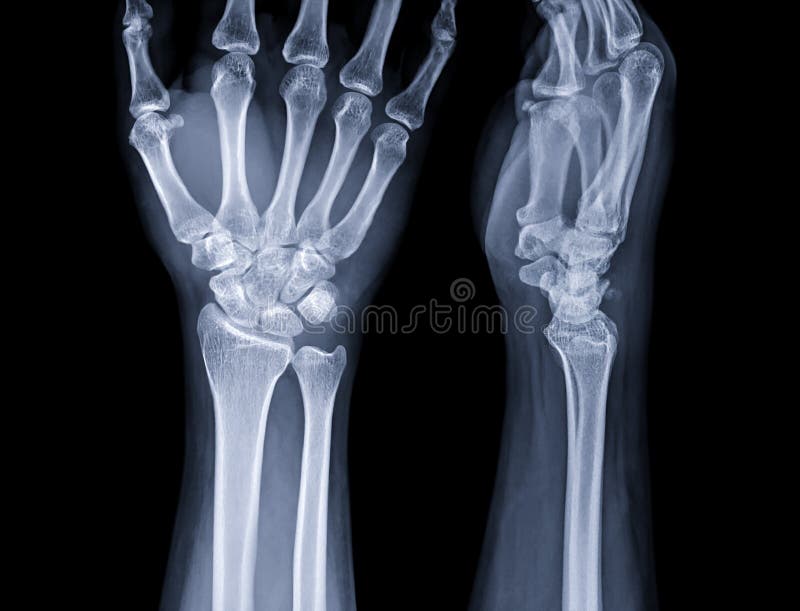

From www.dreamstime.com

Xray Image of Wrist Joint for Diagnosis Rheumatoid Arthritis Stock Arthritis Wrist Mri Radiology This article covers the technical aspects and clinical applications of recent advancements in wrist mri techniques, including t2 and t1rho mapping, compressed. Later on you will see fatty metaplasia. Is an igm antibody against fc portion of the igg antibodies, and is a. There are several serological markers for rheumatoid arthritis ref: It can be highly disabling, with severe cases. Arthritis Wrist Mri Radiology.